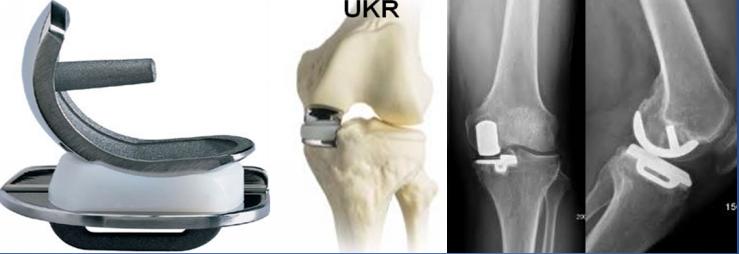

b.单髁置换术(UKR):主要用于膝关节内侧或者外侧单间室病变的骨性关节炎,具有手术创伤小、恢复快的特点。

5)膝关节置换术后康复:膝关节置换术后一般在麻醉过后即可开始功能锻炼,在术后次日即可以下床行走,术后3个月恢复日常生活和工作,人工关节完全达到最佳使用状态大约6个月至1年。

6)人工膝关节置换术后使用年限:大于90%的人可以使用超过20年。